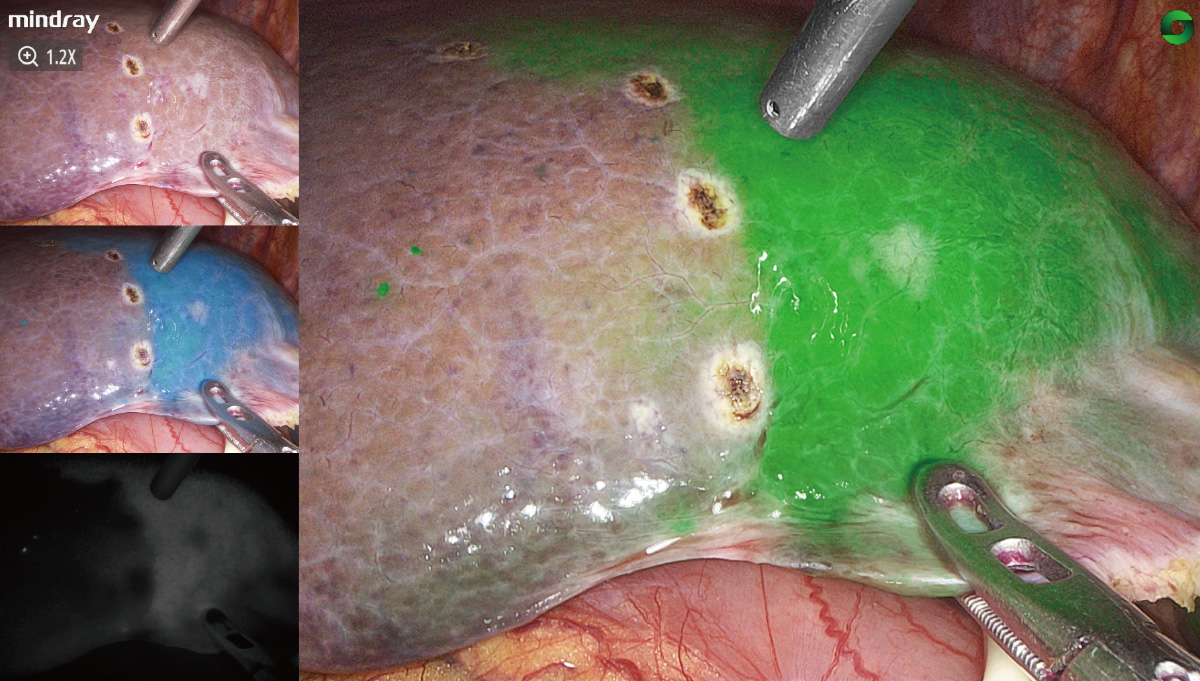

PercepciĂłn sensiblenavegaciĂłn precisa

El avance en la tecnologĂa de fluorescencia aumenta significativamente la sensibilidad de detecciĂłn y la estabilidad de la imagen de fluorescencia, lo que hace mĂĄs precisala navegaciĂłn.

El avance en la tecnologĂa de fluorescencia aumenta significativamente la sensibilidad de detecciĂłn y la estabilidad de la imagen de fluorescencia, lo que hace mĂĄs precisala navegaciĂłn.

Algoritmo de estabilizaciĂłn de la fluorescencia

VisualizaciĂłn precisa del ĂĄrea de imagen con verde de indocianina, eliminaciĂłn eficaz de la atenuaciĂłn de se?al causada por la distancia y la desviaciĂłn del ĂĄngulo, gran estabilidad de la fluorescencia y adecuada divisiĂłn de los mĂĄrgenes.

FusiĂłn de fluorescencias a nivel de pĂxel

El estricto control del proceso de montaje ayuda a obtener la fusiĂłn y alineaciĂłn pĂxel a pĂxel de la imagen de luz blanca y fluorescencias. La imagen de fluorescencias con detalles de textura de luz blanca tambiĂ©n puede ayudar en todo el proceso quirĂșrgico guiado por fluorescencia

Casos clĂnicos

La resecciĂłn hepĂĄtica laparoscĂłpica (RHL)

Mapeo de ganglio linfĂĄtico centinela en cĂĄncer de endometrio